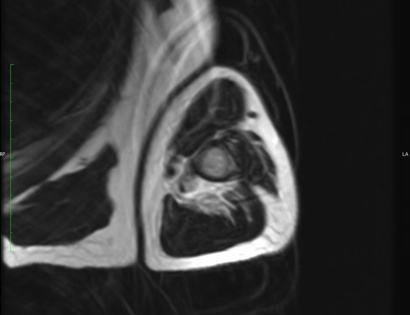

MRI of Myeloma

This is an MRI of Myeloma. Advanced imaging such as MRI, or magnetic resonance imaging, is used to help diagnose the disease and show the extent of the disease.